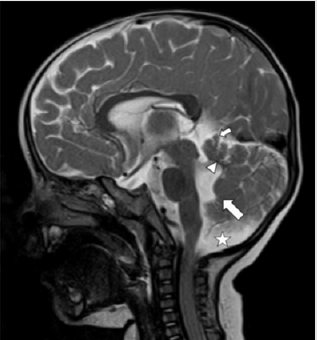

A 1-year-old boy presented to the Paediatrics department of our Institute with global developmental delay and extrapyramidal features. He was a term child born out of consanguineous marriage with an uneventful birth and family history. On examination, the infant was found to have nystagmus. No other ocular anomalies were present. No polydactyly or oro-facial defects were visualized. The patient was referred for MRI examination of brain in our Radiology Department which was carried out under sedation in Siemens Magnetom Aera 1.5 T MRI scanner. Axial MRI sections of brain revealed the characteristic “Molar Tooth” appearance of midbrain (Figure 1) with “Batwing Shaped” fourth ventricle. The cerebellar vermis was severely hypoplastic, dysmorphic and clefted (Figure 2). Sagittal MRI sections of brain showed small dysmorphic vermis with an elongated fourth ventricle. The roof of the fourth ventricle was convex upwards with an “enlarged rounded fastigial point”. Note was made of enlarged retro cerebellar space (Figure 3).

Figure 3: Mid Sagittal T2WI MRI section of brain of the infant with Joubert Syndrome showing small dysmorphic vermis (small arrow) with an elongated fourth ventricle. The roof of the fourth ventricle is convex upwards (arrowhead) with an “enlarged rounded fastigial point” (larger arrow). Note the enlarged retro cerebellar space (star).

MRI is the primary imaging modality for diagnosis of Joubert Syndrome. “Molar tooth sign” is a mandatory and classical imaging feature seen on axial sections of brain. It is attributed to the malformation of midbrain and hindbrain where elongation and thickening of the superior cerebellar peduncles is seen along with a deep inter-peduncular fossa [1–3, 5]. Absence of decussation of fibres of superior cerebellar peduncles is the cause of deep interpeduncular fossa of mid brain. Using diffusion tensor imaging, this has been well illustrated via fibre tracking by Poretti et al [6]. Functional MRI has provided complementary information by recording abnormal activation patterns of brainstem nuclei. The other significant imaging feature of the disease includes “Clefted Vermis” with a “batwing Appearance” of Fourth ventricle. Midline sagittal sections of MRI show a small vermis which is dysmorphic with a deformed forth ventricle. The fourth ventricle is elongated, shows upward convexity of its roof and an enlarged rounded fastigium. Our case showed all these classical features of Joubert Syndrome on MRI imaging.Additional infratentorial manifestations include enlargement of the posterior cranial fossa, increased retrocerebellar CSF space along with hypoplastic as well as dysplastic cerebellar hemispheres.